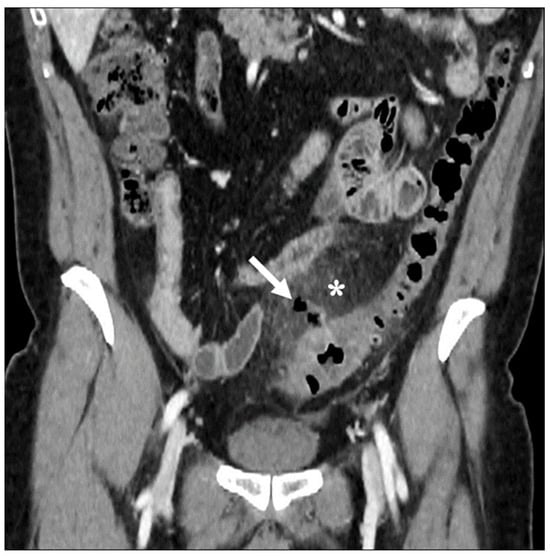

Figure 1. Axial contrast-enhanced CT images show acute left colonic diverticulitis and associated findings of perivisceritis (a,b). Once the longitudinal axis of the colon is identified (green straight line in (a)), bowel wall thickness is measured perpendicular to the centerline (9.6 mm, red segment in (a)), showing an increase in the maximum distance from the serosal-to-mucosal surface. Additional mesenteric findings (b), such as increased density of pericolic fat (arrow), thickening of latero-conal fascia (“comma sign”) (arrowhead), and abdominal free fluid (asterisk), are found.